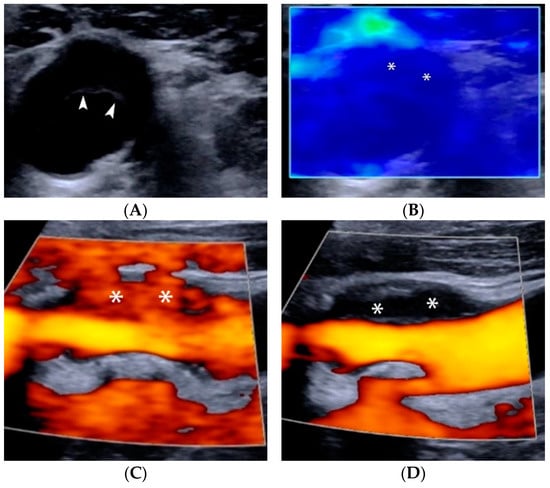

4.1.1. Intraplaque Neovascularization

4. Contrast-Enhanced Ultrasound (CEUS)